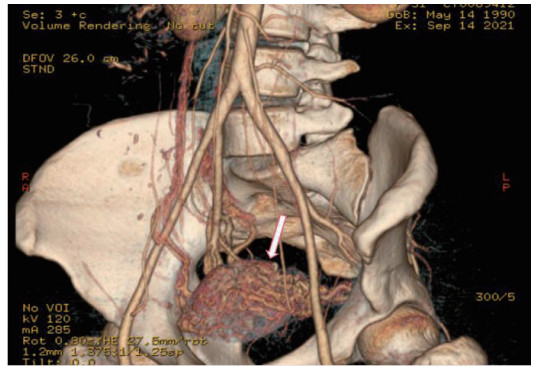

2.4 CTA检查与DSA检查非保守治疗患者中26例患者行CTA检查(图 4),24名提示UAVF, 诊断敏感率为92%。联合TVDU可确诊25名,既CTA、超声联合诊断UAVF的敏感率为96%。非保守治疗的34例患者DSA检查均诊断UAVF。

| 图 4 子宫动脉CTA血管造影:子宫动脉血管迂曲增粗成团(白色箭头) |

CTA对动脉和静脉来源出血均敏感[14],可显示UAVF畸形血管三维空间结构[6],诊断敏感度达92%,特异度达100%,如联合TVDU,敏感度可高达96%,是理想的诊断方法。